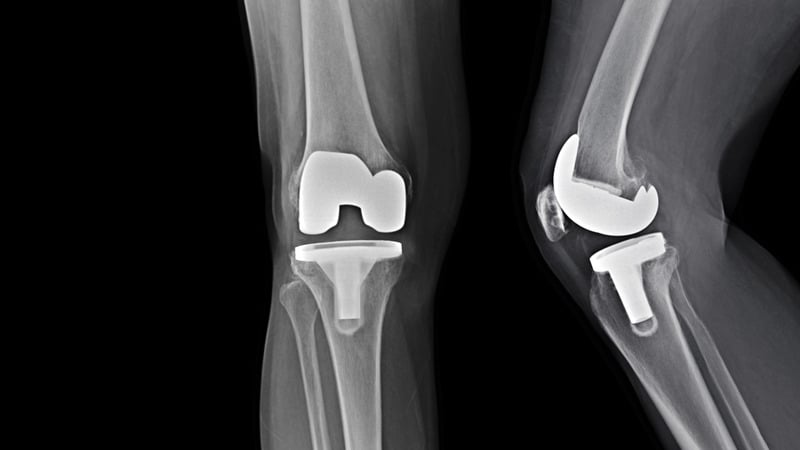

• Αρθροπλαστική Γόνατος: Όπως και η αρθροπλαστική ισχίου, αυτή η επέμβαση περιλαμβάνει την αντικατάσταση της κατεστραμμένης άρθρωσης του γόνατος με

ένα τεχνητό εμφύτευμα. Υπάρχουν διάφοροι τύποι αρθροπλαστικής γόνατος, όπως η ολική και η μερική αρθροπλαστική.